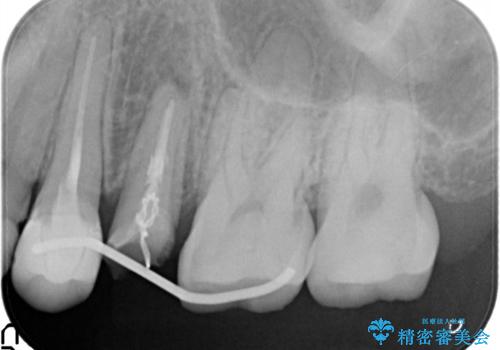

かぶせ物と詰めてある修復物を除去すると歯肉の中まで虫歯になっていました。

歯を部分矯正で引き上げて、虫歯を徹底的に取り除き、適合の良いかぶせ物を装着する計画としました。